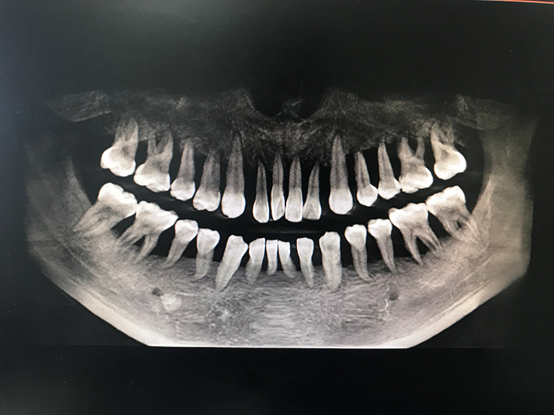

“我從醫(yī)這么多年也是第一次見到如此嚴(yán)重的牙周炎患者。”接診醫(yī)生周矗說,從小周的口腔檢查中發(fā)現(xiàn),他的全口牙齒都有牙齦的膿腫,伴有嚴(yán)重的骨頭萎縮以及吸收,所有牙齒幾乎都是3度松動(dòng),并且口腔異味特別嚴(yán)重,牙齒上附著大量牙結(jié)石及食物軟垢。